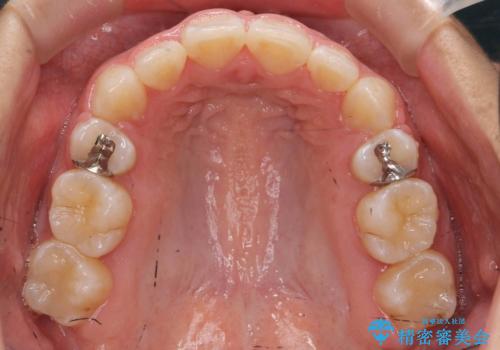

前歯のがたがた 前歯が内側に傾いている

上の歯並びが前にずれて、さらに前歯が内側に倒れて過蓋咬合を呈していました。